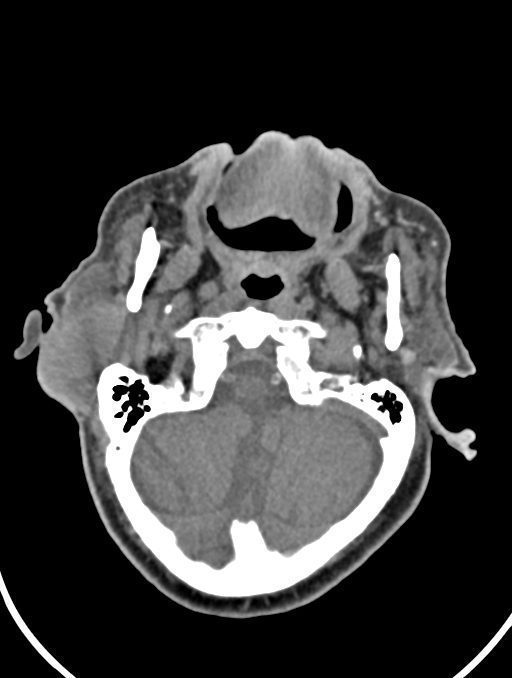

در سي تي اسکن اسپيرال نازو فارنکس با و بدون کنتراست (مولتي ديدکتور 16 با مقاطع ظريف و بازسازي هاي ساژيتال و کرونال):

– توده نسج نرمي به ابعاد mm 40 x 45 x 60 در ناحيه پاروتيد راست، با enhancement هتروژن پس از تزريق کنتراست مشهود است که مطرح کننده آدنوم پاروتيد مي باشد.

– شواهدي از تهاجم توده به استخوان و عروق اطراف مشهود نيست .

– کلسيفيکاسيون در ديواره شريان هاي کاروتيد دو طرف مشهود است .